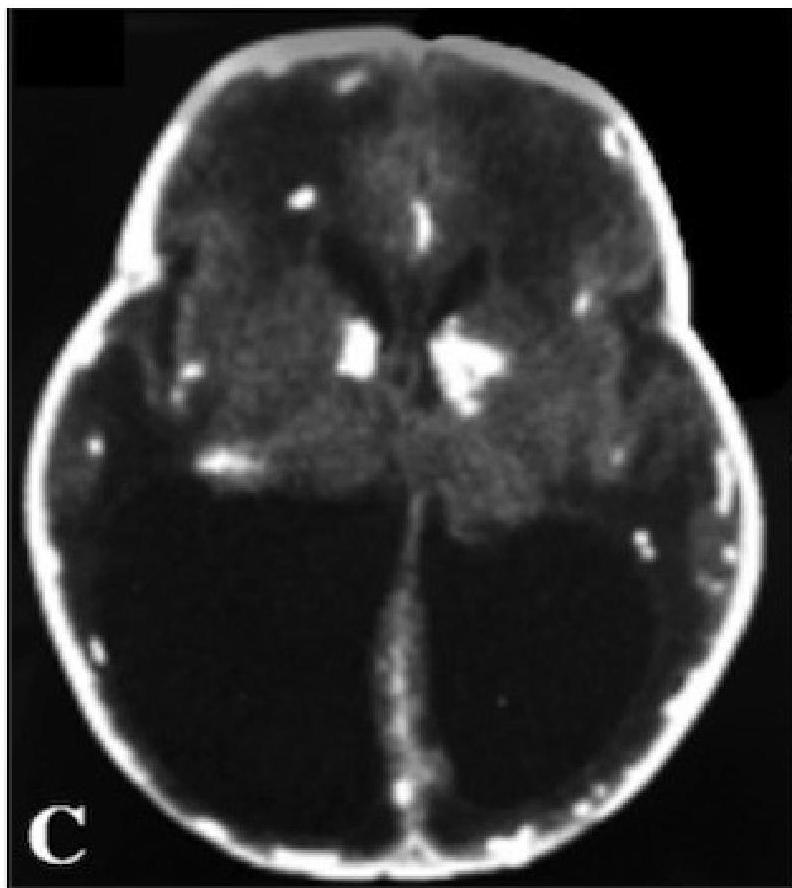

- Leads to: Inflammation, Cellular destruction, Calcification (especially in periventricular areas of the brain).

- Neurological: Microcephaly, Seizures, Intracranial calcifications (classically periventricular).

Ventriculomegaly and calcification of congenital CMV

- Imaging: Cranial ultrasound/CT → periventricular calcifications, ventriculomegaly.